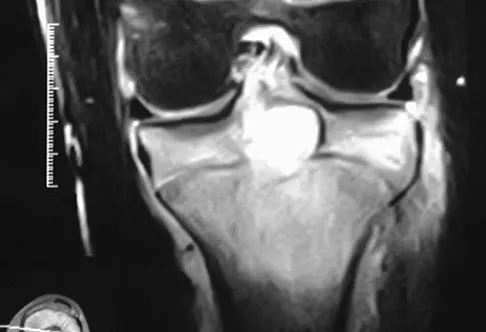

Figure 50 shows the MRI scan of a 20-year-old female college soccer player with knee pain. What is the most likely diagnosis?

Anatomy Board Review 2002: High-Yield MCQs (Set 4) - Figure 13

Explanation

The MRI scan shows an acute complete tear of the posterior cruciate ligament. No evidence is seen of a quadriceps tendon rupture, a tibia fracture, or a bone contusion. Beaty JH (ed): Orthopaedic Knowledge Update 6. Rosemont, IL, American Academy of Orthopaedic Surgeons, 1999, pp 533-557.